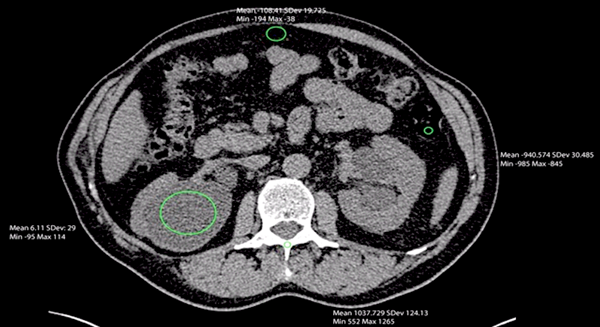

Figure 1: Unenhanced axial CT abdomen demonstrating the use of Hounsfield units.

Figure 1 shows an axial, unenhanced CT image of the upper abdomen, demonstrating different Hounsfield units of bone (HU 1037), air in the colon (HU -940), a cyst in the right kidney (HU 6) and peritoneal fat (HU -108). Hounsfield units can be used to characterise renal stones, with a uric acid stone having a lower Hounsfield unit than a calcified stone. A calculus >1000HU is more likely to be calcium and <500HU more likely to be uric acid. Previous studies have shown that extracorporeal shock wave lithotripsy (ESWL) is more successful, requiring less number of shock waves and sessions, in calculi with HU 750 or less [4].

In order to measure a calculus using HU, the reporter must place a region of interest over the area to be measured and the mean HU value, maximum and minimum HU values and standard deviation will then appear on the screen. If a large region of interest is used, the maximum and minimum values may greatly differ. If the structure to be measured is small, as is often the case in renal tract calculi, it can be difficult to accurately place the region of interest. Mixed composition stones may give an inaccurate reading, making interpretation difficult. Previous studies have shown that there can be an overlap of attenuation values when used for characterisation of renal calculi, leading to a lower specificity [5].